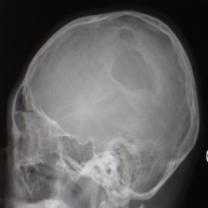

頭顱正側(cè)位片:可見右頂部顱骨缺損區(qū),局部軟組織隆起,類長圓形,缺損邊緣不規(guī)則、骨質(zhì)密度增高合并骨質(zhì)破壞密度減低,隆起如火山口狀(圖1)。

圖1:(1)正位相見右頂部骨質(zhì)缺損,局部軟組織隆起,邊緣不規(guī)則,骨質(zhì)密度增高合并骨質(zhì)破壞密度減低,隆起如火山口狀;(2)側(cè)位相見顱骨缺損區(qū),類似長圓形,缺損邊緣不規(guī)則